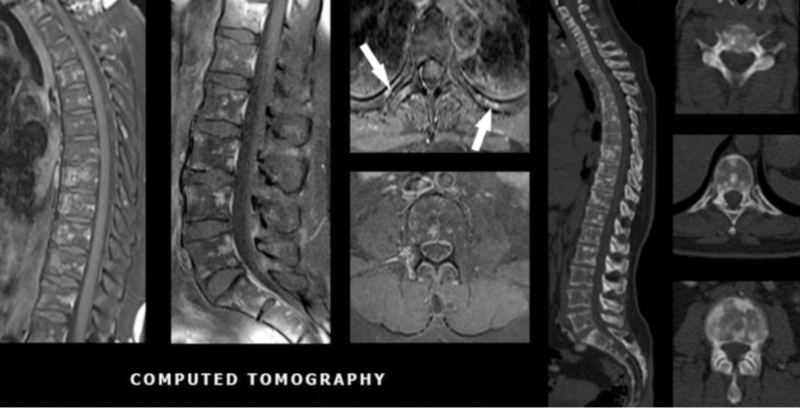

Tomografia computadorizada de tórax (fig. 2) e ressonância magnética (fig. 3), evidenciaram múltiplas formações nodulares ósseas aleatoriamente distribuídas em arcos costais e corpos vertebrais torácicos e lombares, sem sinais de fraturas patológicas. Biópsia (fig. 4) e estudo imunohistoquimico (fig. 5) foram realizados; a análise histológica revelou medula óssea com celularidade preservada e sem evidência de malignidade. A imunohistoquímica (IHQ) demonstrou expressão para CD3 e CD20 sem expressão de citoqueratina, sugerindo tecido hematopoiético reacional e excluindo neoplasia secundária.

Apesar da localização incomum das lesões, osteopoiquilose foi considerada o principal hipótese diagnóstica devido à ausência de lesões hipermetabólicas em PET/CT(5) e à baixa captação do radiofármaco na cintilografia óssea(6), além da ausência de indícios de malignidade na biópsia e da negatividade da IHQ para biomarcadores tumorais(7).

Nesta paciente, a cintilografia óssea mostrou leve aumento inespecífico de 99mTc-MDP em processos espinhosos de coluna lombar, articulações sacroilíacas, articulações do quadril e côndilos laterais do fêmur. Esse achado foi compatível com doença degenerativa osteoarticular. Biópsia de região pélvica e imunohistoquímica também foram realizadas e evidenciaram tecido hematopoiético reacional, excluindo neoplasia secundária.